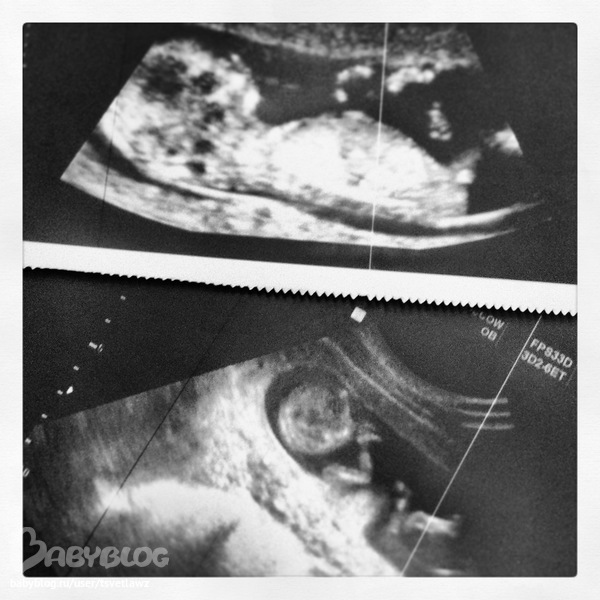

А это наш малышок:

Под конец исслеования малыш угомонился и спокойно лежал, посасывая свой большой пальчик... надо ли писать, что у нас с Любимым в этот момент глаза были на мокром месте ))))